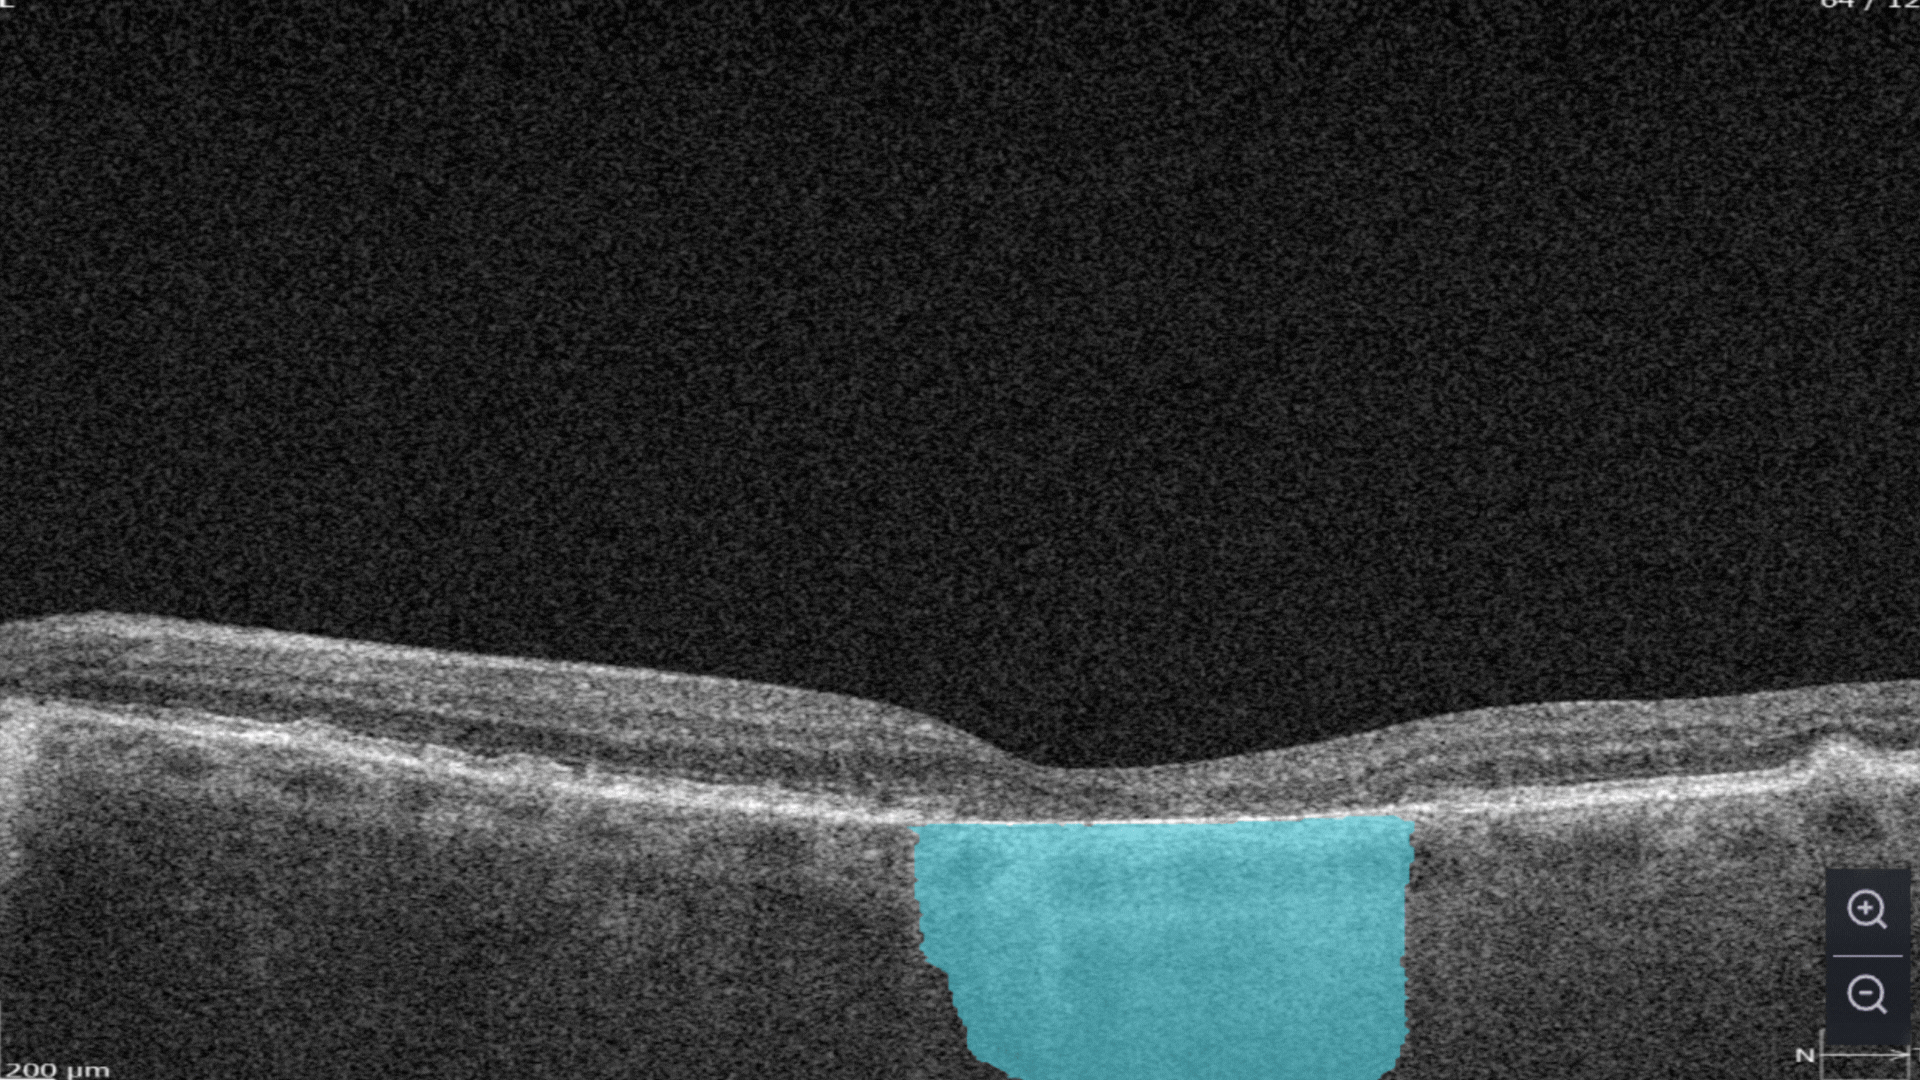

AI automates the selection of pathological OCT scans and the detection of 70+ pathologies and biomarkers.

More detailed screening means more early cases detected and more effective treatment as a result.